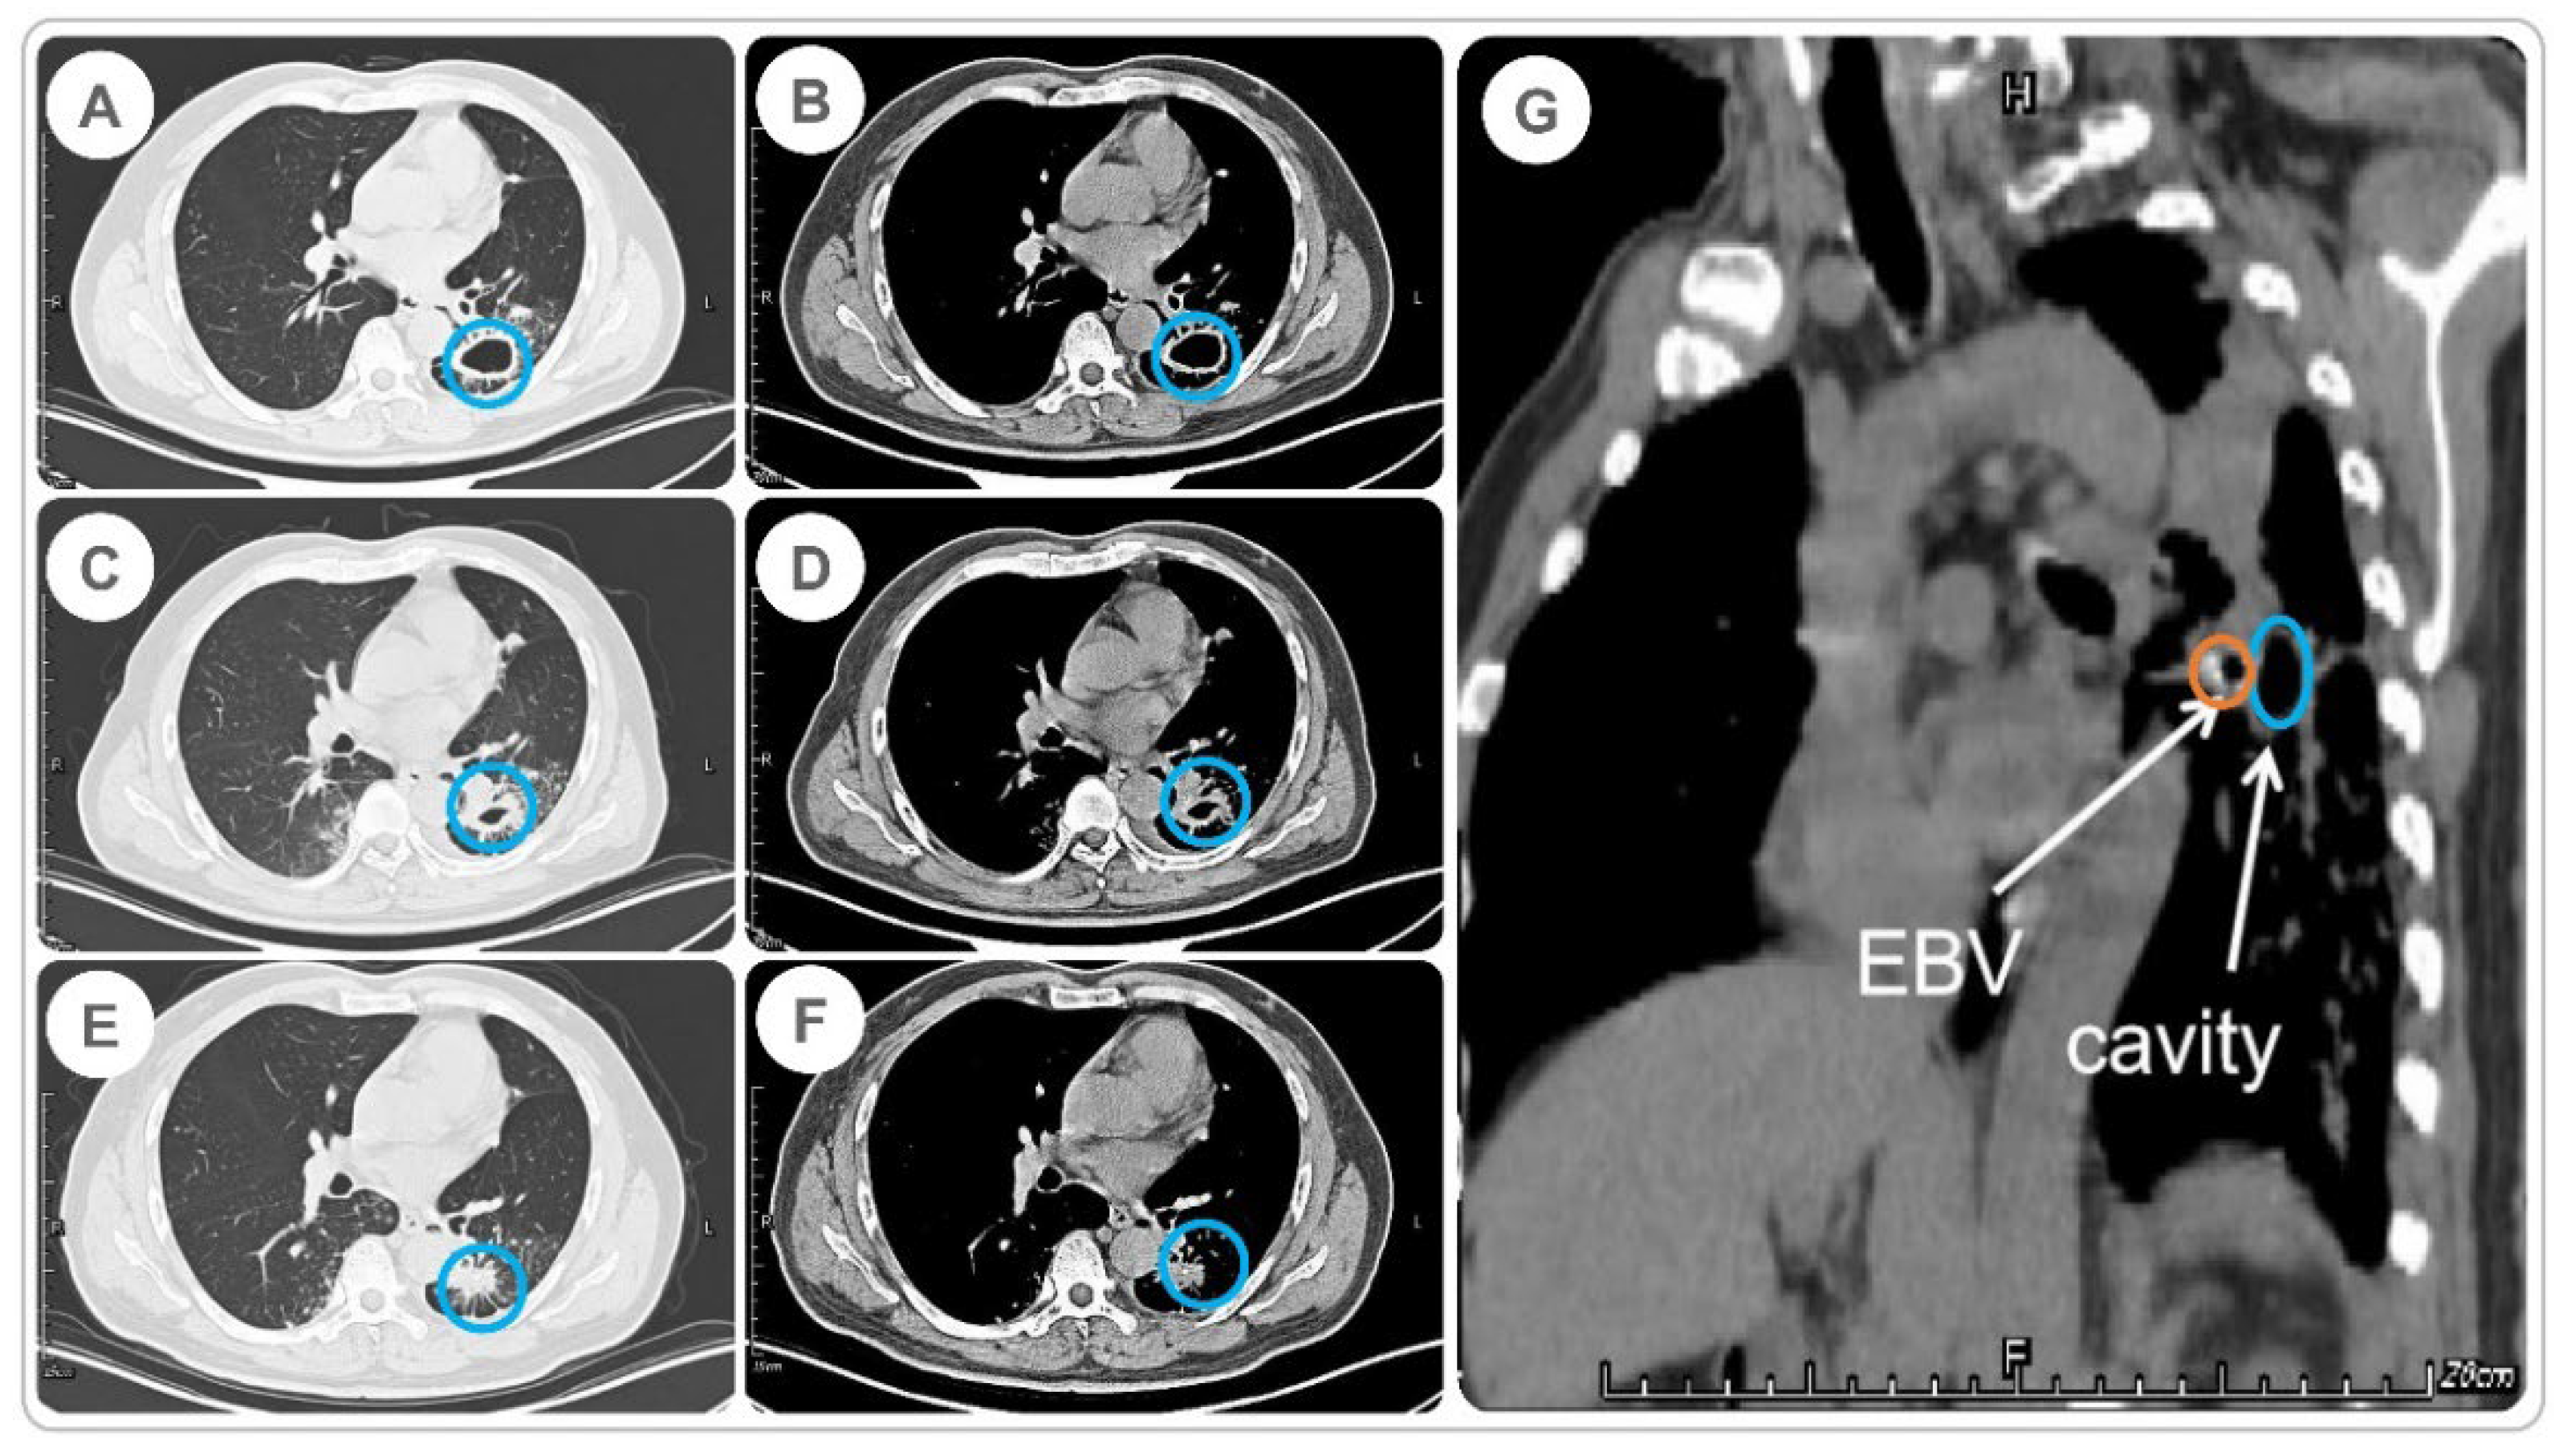

2.3. Time to Cavity Closure and SCC in MDR-PTB Patients after EBV Treatment

Figure 3. Cavity changes before and after EBV implantation in an MDR-PTB patient. (A) Cavity size (lung window) before EBV implantation on 2 August 2017; (B) size of the cavity (mediastinal window) before EBV placement on August 2, 2017; (C) size of the cavity (lung window) four days after EBV implantation on 14 August 2017; (D) size of the cavity (mediastinal window) four days after EBV implantation on 14 August 2017; (E) size of the cavity (lung window) 60 days after EBV implantation on 18 October 2017; (F) size of the cavity (mediastinal window) 60 days after EBV implantation on 18 October 2017; and (G) the EBV and cavity in the mediastinal window. The cavity and implanted EBV are highlighted with blue and yellow circles, respectively.